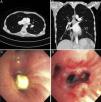

A 44-year-old female with malnutrition, myopathy secondary to disuse or malnutrition, and mast cell activation syndrome initially presented with a 3-month history of worsening shortness of breath and occasional cough. She was referred to bronchoscopy after being found to have an endobronchial lesion on chest computed tomography (Fig. 1, top panel). A clinical suspicion of endobronchial carcinoid was raised due to persistent and severe diarrhea. Flexible bronchoscopy revealed a foreign body in the bronchus intermedius (Fig. 1, bottom panel) which was removed using a wire basket. Extensive granulation tissue was noted in the bronchus intermedius around the foreign body and copious purulent secretions were aspirated. The size and appearance of the foreign body was consistent with the patient's calcium citrate once-a-day pill; however, she did not recall the aspiration event. Aspiration of multivitamin or calcium tablets is rarely reported,1,2 possibly due to their size. It is not known whether a calcium pill may spontaneously dissolve if the patient is unable to cough it up. In our patient, the high radio-density (mean 576 Hounsfield Units) and its sharp edges suggested pill aspiration.